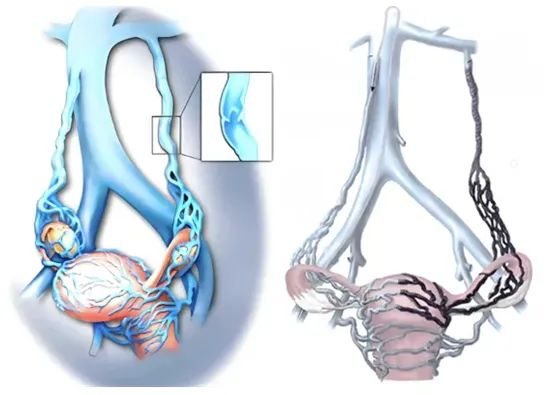

盆腔淤血综合征是一种以盆腔疼痛、性交痛、尿急等为表现,病史>6个月的临床综合征,是由卵巢静脉、盆腔静脉反流或者阻塞引起的,可以伴有外阴、会阴、下肢等部位浅静脉曲张。特征性的临床表现为“三痛、两多、一少”,即盆腔坠痛、低位腰痛、性交痛、月经和白带增多和妇科检查阳性体征少。

由于PCS致病因素的多样性,目前其引发CPP的具体机制仍不明确。目前介入治疗已经成为PCS首选的治疗方法。介入腔内治疗具有微创、病人舒适度高、住院周期短、并发症少等优点,对于原发性反流性PCS,栓塞治疗主要是栓塞引起反流的静脉以及宫旁静脉,目前已经被多项研究证实其安全、有效,术后达到60%至100%的症状缓解率。